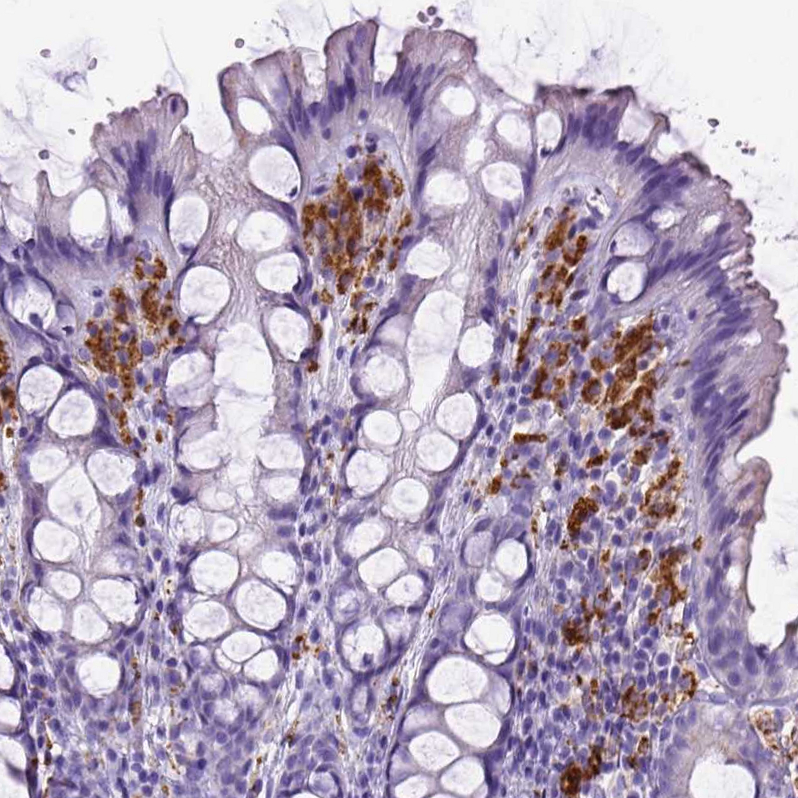

Immunohistochemistry analysis in human lung and skeletal muscle tissues using AMAb90874 antibody. Corresponding CD68 RNA-seq data are presented for the same tissues.